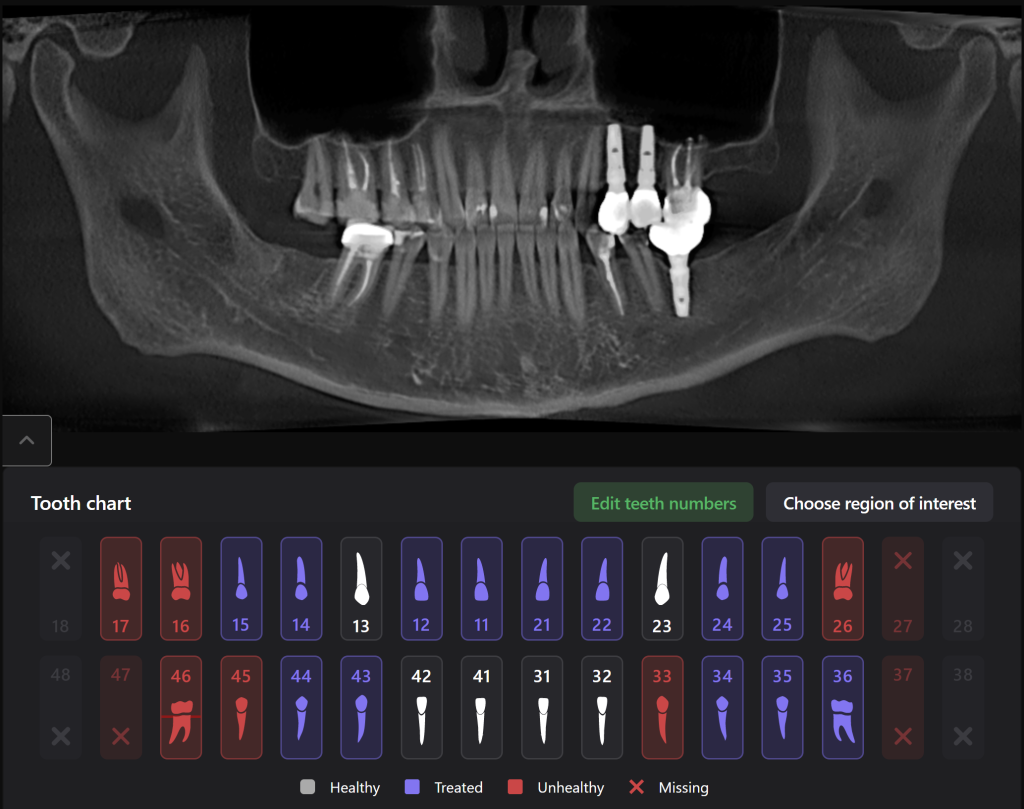

Planning implant placement using Diagnocat modules can help save the clinitian’s time and enhance the quality of implantological treatment

The decision has been made to perform immediate implant placement to replace teeth 24 (Universal 12) and 25 (Universal 13).The optimal position of the future implant is planned by starting with intraoral scanning and importing digital models into the Diagnocat STL module

3D reconstruction created on the basis of DICOM and an intraoral scan in the Diagnocat STL module allows you to choose the optimal size and location of the implants